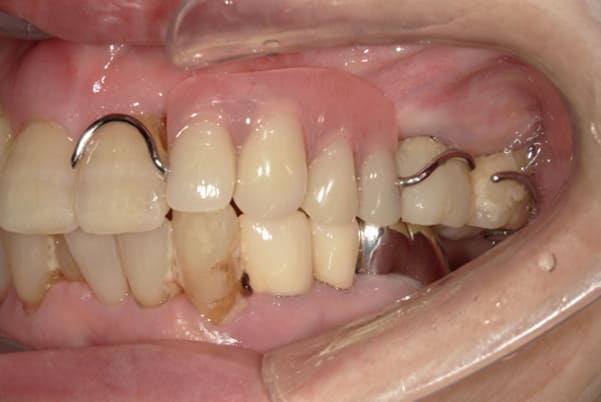

治療前の入れ歯の奥歯は、治療後の義歯と比較しても分かるように、歯が削れ平らになった状態です。

これにより奥歯のかみ合わせは低くなり、前歯のみが強くあたり、かみ合わせにより上の前歯大きな負担がかかっていたことにより、上の前歯が折れたことが考えられます。

治療前は、奥歯が下がり、かみ合わせが乱れています。適切な入れ歯はそのままのかみ合わせで義歯を作るのではなく治療後のように、前歯から奥歯までのラインが真っすぐ揃った、かみ合わせの面を適切に付与し、よく咬め、残りの歯に負担がかからないかみ合わせとしました。